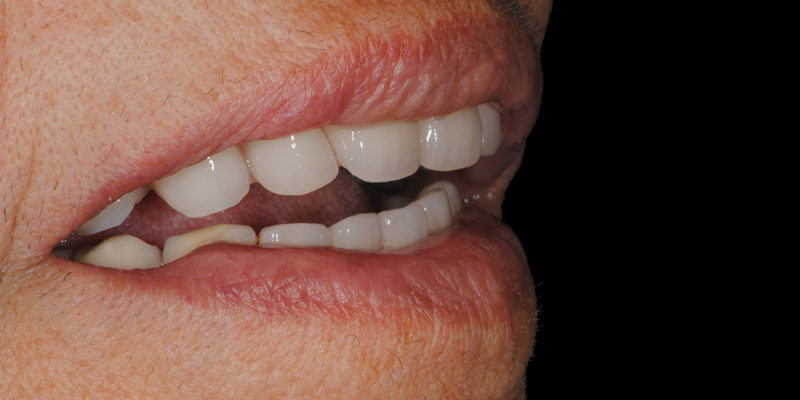

Ripristino dell’arcata superiore su overdenture su barra